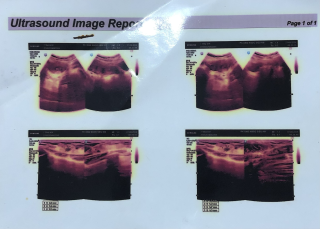

O Hoàng Thị Thư sinh năm ngày 10/2/1984. O bị ung thư vú vào viện mổ ngày 17/10/2025 trong tình trạng khối u đã lan rộng và bị vỡ, O đang trong liệu trình hoá trị nhưng O đã xin ngưng điệu trị vì do sức khoẻ đã quá yếu, bệnh đã di căn (giai đoạn cuối). Hoàn cảnh gia đình đặc biệt khó khăn, không có điều kiện kinh tế, O không có chồng, không có con hiện tại ở nhờ nhà em gái không ai chăm sóc (gia đình em gái cũng khó khăn và đang đi làm xa ở Hà Nội), bản thân O lắng không đủ khả năng lo liệu hậu sự cho mình khi qua đời. Nguyện vọng của O là xin giúp đỡ một áo quan để khi nhắm mắt xuôi tay O được an nghỉ. Sđt O Thư: 0977146168

Chị tên Hoàng Thị Thư. Sn 1984 Chị bị ung thư Vú đã mổ nhưng vì hoàn cảnh gia đình quá khó khăn không có vô thuốc hoá trị. Sau mổ chỉ uống thuốc lá nam nên bệnh tái phát, chị đang ở nhờ nhà em gái ở địa chỉ xóm Xuân đông, Bích hào, Nghệ an. Đt: 0977146168. Hiện tại chị phải vật lộn với những cơn đau ngày một dày hơn.

Vì đau quá nên hôm nay chị đi khám và được bác sĩ thông báo khối u đã di căn nhiều nơi bệnh đã sang giai đoạn cuối. Không có tiền chỉ chỉ lấy thuốc giảm đau rồi ra về trong nước mắt.